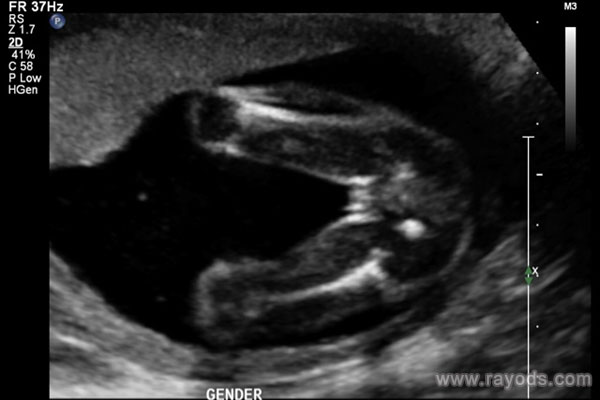

13周b超图男女腿部间真没区别,别看有凸起就瞎说

我们都知道,胎儿的是男孩还是女孩是孕妈妈们非常好奇的事情。在怀孕中期的时候,女性都需要进行B超检查,通过B超检查不仅可以了解胎儿的发育情况,而且还能够判断出胎儿的..

怀孕14周胎儿b超图看男女可以吗?看男女准不准?

在医学领域,b超技术是一种非常重要的检查手段。尤其是在孕期检查中,b超技术能够帮助我们了解胎儿的情况,包括性别。而在14周左右,通过b超图像来判断男女的准确率也比较..

30周b超男女腿部间的区别图 真实b超图片

一般来说,怀孕除了要注意生活中的方方面面之外,为了更好更直观的监测到胎儿各个孕周的发育情况,就需要通过产检来看了。在怀孕3个月的时候会做第一个重要的产检,就是nt..